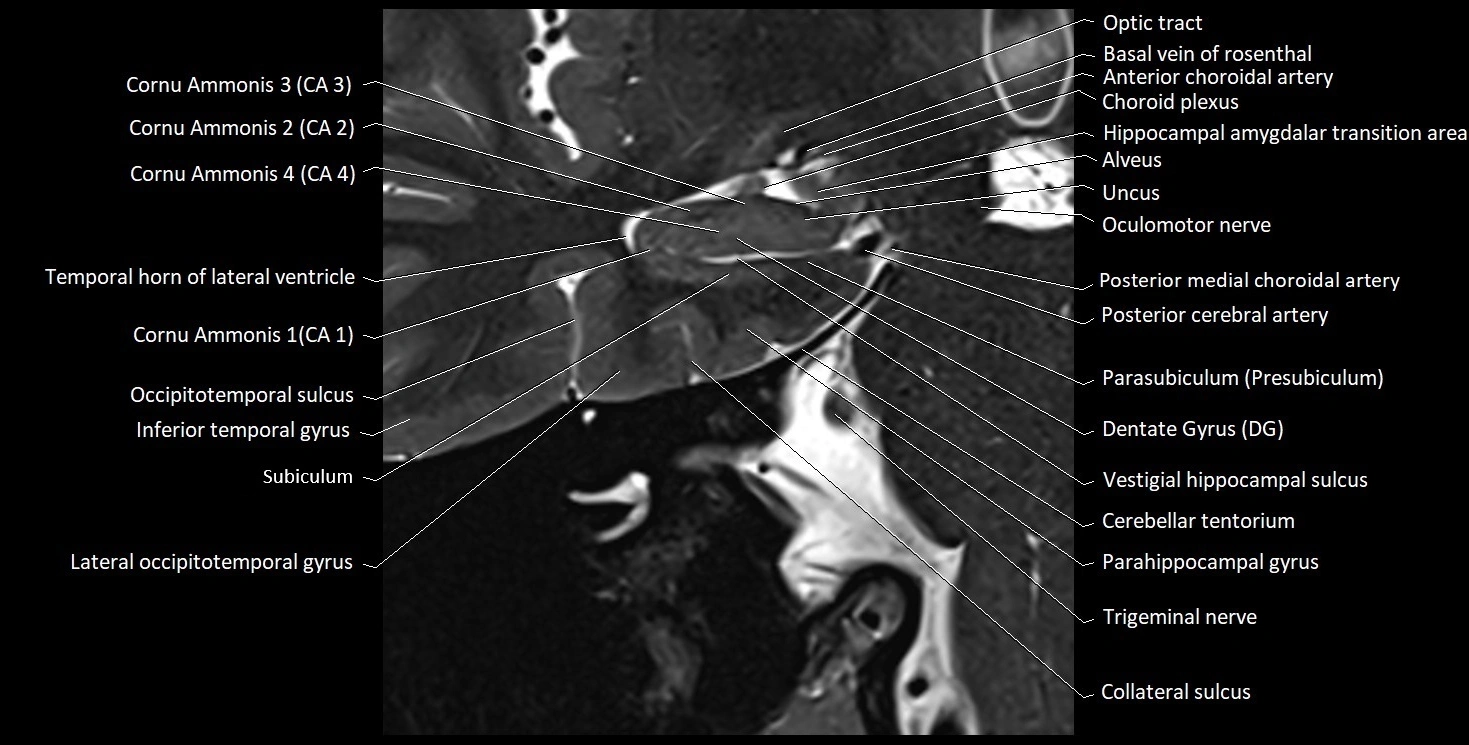

The alveus of the hippocampus is a thin, white matter layer covering the superior (ventricular) surface of the hippocampus within the temporal horn of the lateral ventricle. It consists of myelinated efferent fibers arising primarily from the pyramidal neurons of the hippocampus. These fibers converge medially to form the fimbria of the hippocampus, which continues posteriorly into the fornix, forming a crucial part of the Papez circuit involved in memory consolidation and emotional processing.

The alveus serves as the initial output pathway of the hippocampal formation, linking it to other limbic structures including the hypothalamus, mammillary bodies, and cingulate gyrus. Because of its intimate relationship with the hippocampal head and tail, it is often evaluated in cases of temporal lobe epilepsy, hippocampal sclerosis, and neurodegenerative diseases.

Location and Structure

• Position: Lies on the ventricular (superior) surface of the hippocampus, beneath the ependyma of the inferior horn of the lateral ventricle.

• Composition: A thin sheet of myelinated axons derived mainly from hippocampal pyramidal cells.

• Course: Fibers run medially along the hippocampal surface to form the fimbria of the hippocampus, which curves upward and backward into the fornix.

• Relations:

• Superiorly: Ependyma and CSF of the temporal horn of the lateral ventricle

• Inferiorly: Pyramidal cell layer of the hippocampus (CA1 region)

• Medially: Fimbria and fornix

• Laterally: Temporal lobe white matter and parahippocampal gyrus

MRI Appearance

T1-weighted images:

• Alveus: Thin linear high signal band (due to myelinated fibers) overlying the hippocampal gray matter.

• Hippocampal gray matter: Intermediate signal intensity.

• CSF of lateral ventricle: Dark (low signal).

T2-weighted images:

• Alveus: Low signal line overlying brighter hippocampal gray matter.

• CSF: Bright hyperintense.

MRI images

image